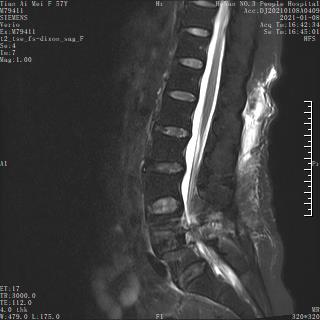

术前MRI

术后MRI